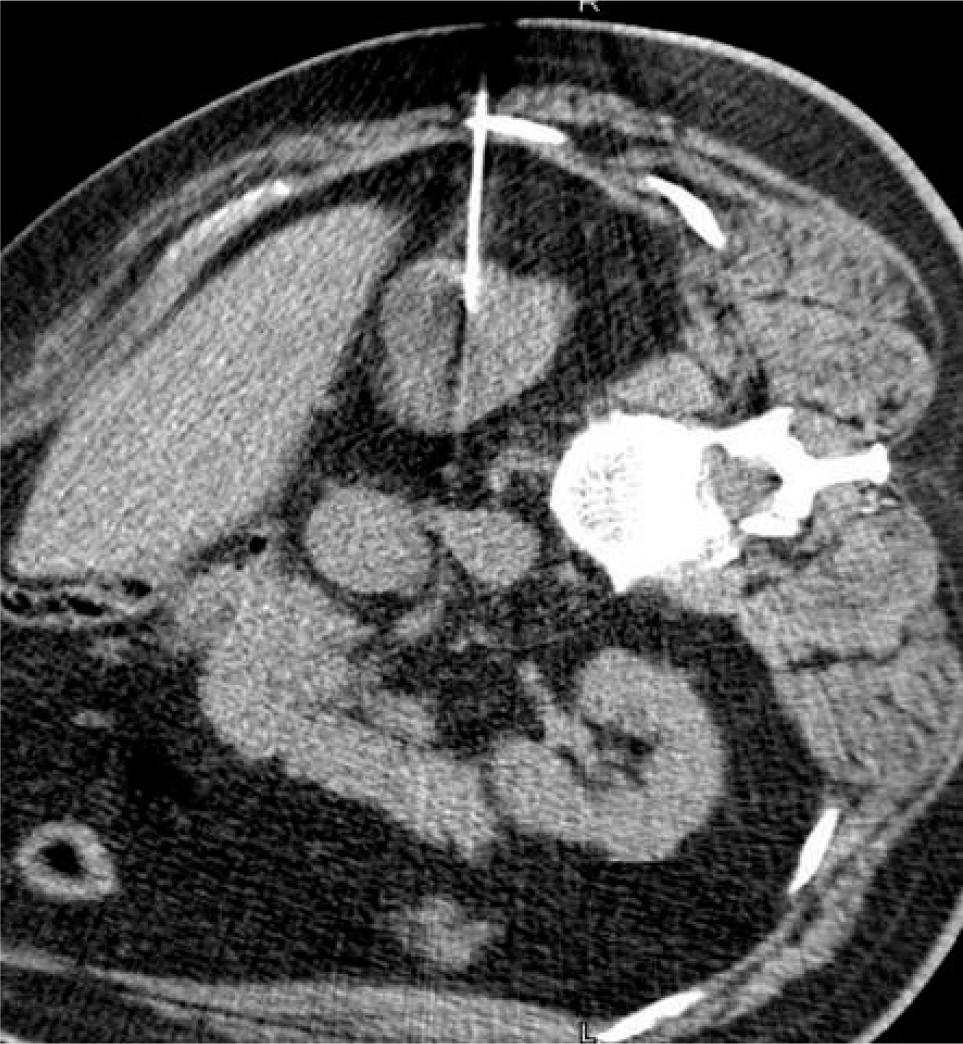

Radiofrequency ablation uses an electrical current in the radio frequency range, between 3 Hz and 300 GHz, to heat tissue resulting in coagulative necrosis. The alternating current is delivered through antennas placed directly into the tumor, with the electrical circuit completed through grounding pads, such as those seen with the Bovie cautery device (24). As current passes through the tissue, heat is generated due to tissue resistance, a concept termed “resistive heating” (Figure 2) (25). Cell death occurs instantly at temperatures above 60°. Notably, effective delivery of RFA relies on the electrical and thermal conductivity in tissue, which can be adversely affected by overheating and desiccation of the tissue directly adjacent to the electrode, resulting in an insulating barrier of charred tissue (26). RFA is often not recommended adjacent to large vasculature, due to inability to overcome the heat sink effect leading to increased risk of incomplete necrosis, possibly impacting oncologic efficacy (27). Over the years, a variety of techniques have been developed to monitor tissue temperature and impedance to limit desiccation and increase the zone of ablation (28). Similarly, multi-tined, expandable, and perfusion electrodes, and bipolar electrode systems are available technologies used to modulate the size and shape of the ablated tissue (26) (Figures 3A–3C).

Figure 3: (A) Multi-tined radiofrequency ablation antenna. (B) Radiofrequency ablation antenna expanded within tumor. (C) Typical tissue changes after successful radiofrequency ablation including pseudo-capsule, subcapsular fat, and nonenhancing lesion.